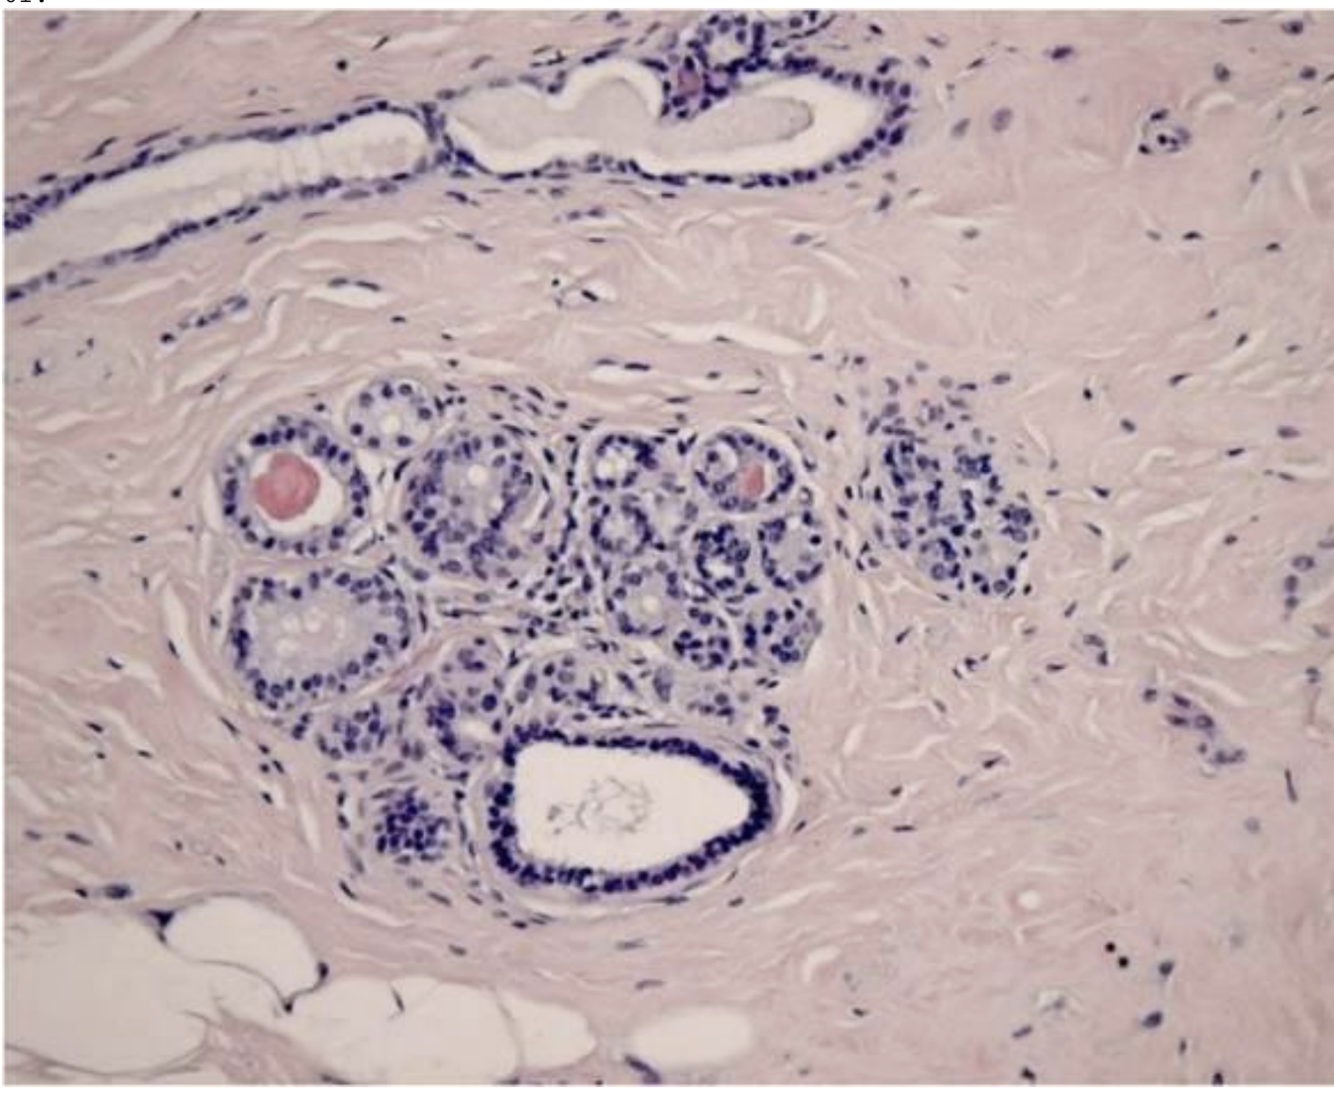

En asiatisk mand på 57 år har symptomer fra maven med dårlig appetit, smerter, kvalme og opkastning. Ved gastroskopi (kikkertundersøgelse af mavesækken) ses ingen overfladeforandringer, men der tages flere, dybe ventrikelbiopsier. Figur A viser del af ventriklens muscularis med grupper af celler, som på figur B er immunfarvede med cytokeratin.

Hvad viser biopsien?

*e. adenokarcinom i ventrikelvæggen